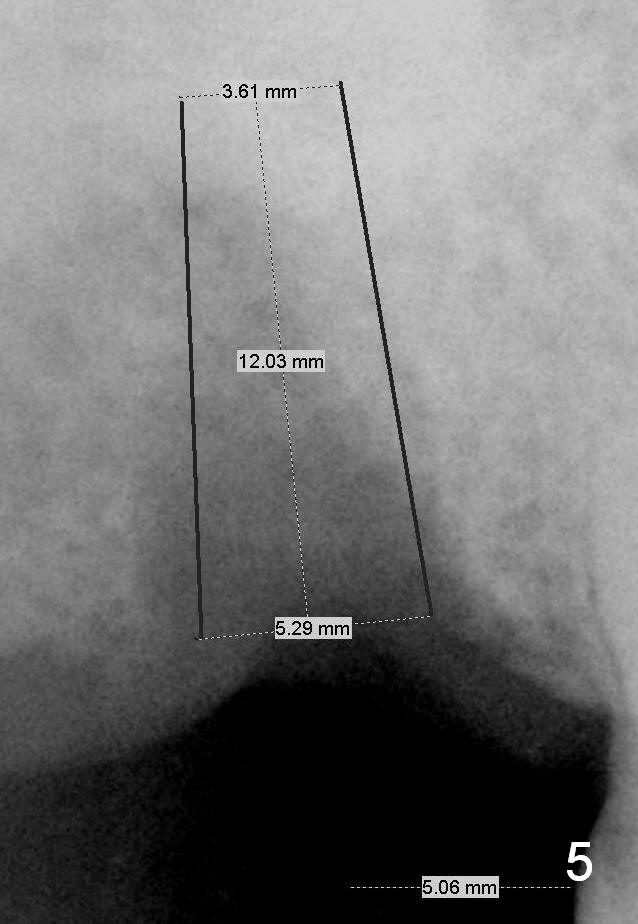

The smallest implant could be 5.3 mm (Fig.4,5). The short (10 mm, Fig.4) and long (12 mm, Fig.5) may be below and above the sinus floor, respectively.